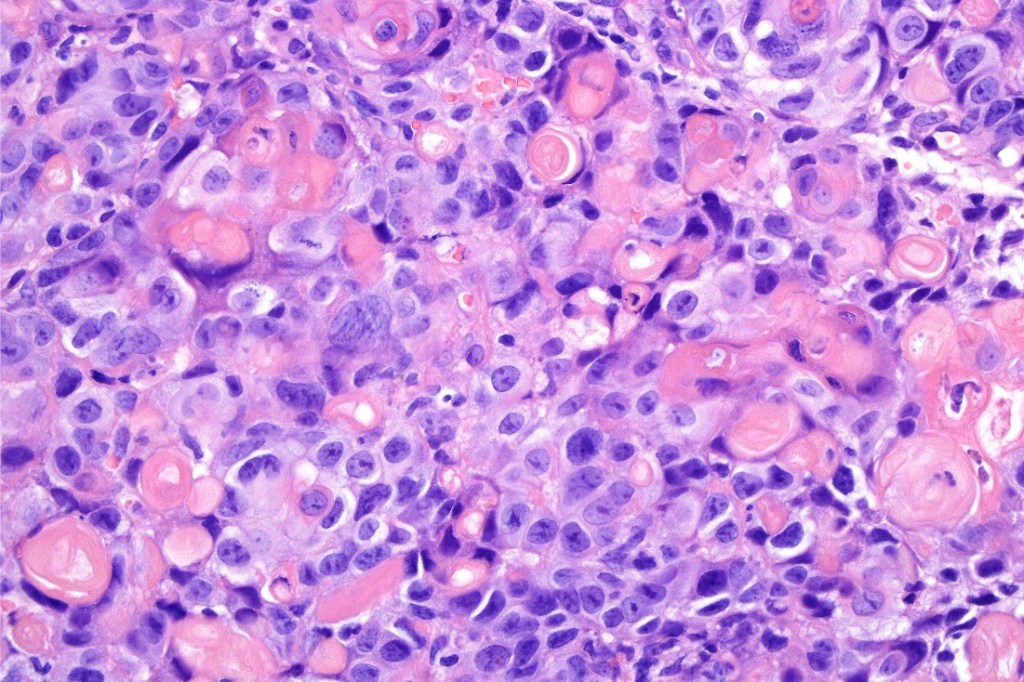

Immunohistochemistry (images from Professor Wayne Grayson’s case)

•Beta-catenin, P-cadherin, E-cadherin +ve

•AE1/AE3 (image1), CK5/6 positive

•Dendritic cells S100 (image 2), Melan-A, HMB45 +ve (image 3),